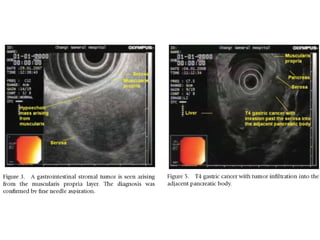

Submucosal Gastric Tumor

Biopsy this?